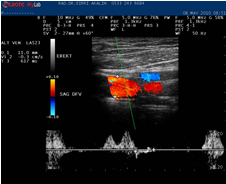

CİHAZ; Esaote Mylab25, portable color doppler